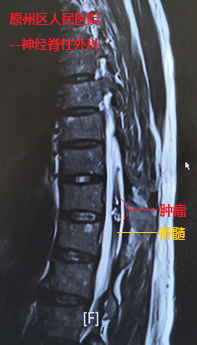

经检查发现,在史伯伯的胸椎脊髓内,长有信号混杂不均的血管性肿瘤,并随着肿瘤出血膨胀,几乎占据了整个脊髓,导致患者一侧下肢近远端肌力完全丧失(0级),另一侧下肢也仅能勉强移动(2-3级)。当地医院神经脊柱外科主任万欣龙判断,史伯伯得的可能是脊髓髓内的海绵状血管瘤并发出血卒中,如若不进行手术,随着肿瘤出血后脊髓水肿的加重,病情将进一步恶化。

我院神经外科援宁队员郑小斌在查看患者并详细阅片后,组织了疑难病例讨论,考虑到患者血管性肿瘤体积大,且生长时间长达十余年,导致该肿瘤与周围脊髓组织的血供情况复杂,最终决定采用显微镜下经脊髓外侧沟切开脊髓并暴露肿瘤。郑小斌介绍,术中对肿瘤与脊髓边界的分离是手术的关键,加上患者脊髓功能受损严重,手术操作既要精细轻柔,也需连贯稳定。经过近2个小时不间断的显微镜下操作,肿瘤顺利从脊髓内切除,周围的脊髓的正常结构得到保护。鉴于肿瘤体积大,出血后脊髓水肿严重,同期给予行脊柱椎板切除减压手术,并进行内固定手术加强脊柱的稳定性,手术顺利完成。